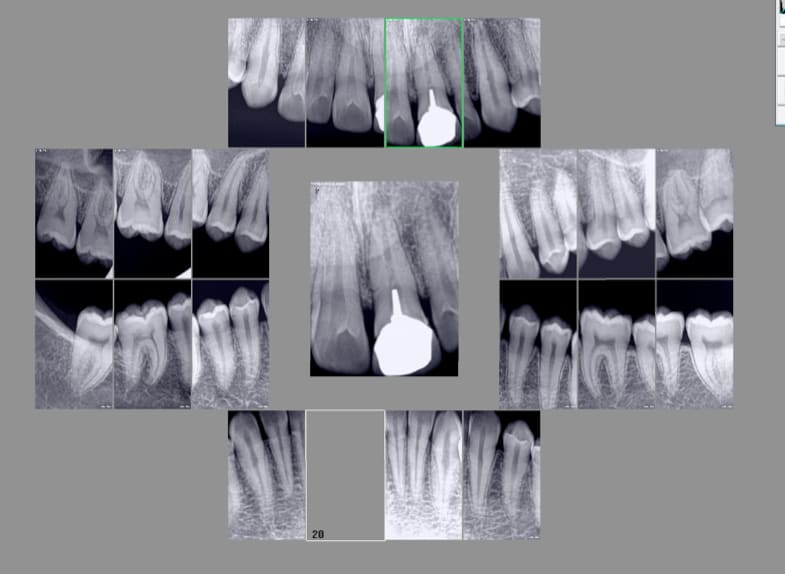

Là un pano est indiqué....... mais ne remplace pas les rétro coronaires et les rétro alvéolaires. -)